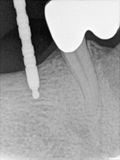

fredlibc | all galleries >> Galleries >> JLin - 46 implant > R1.jpg

R1.jpg